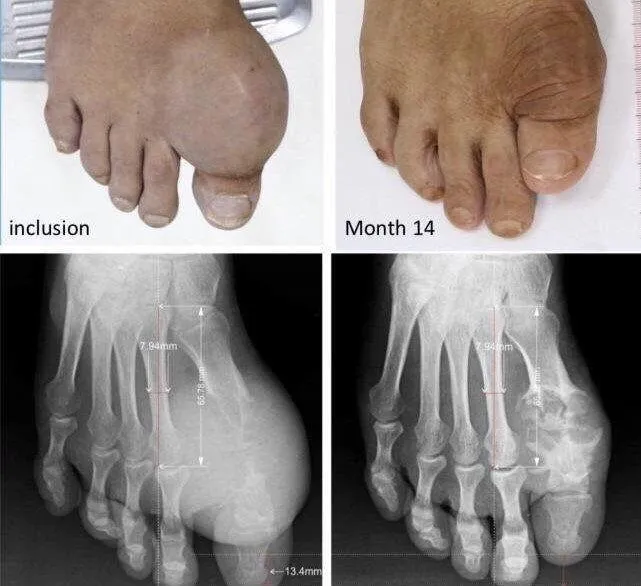

| Phần khớp xương bị phá hủy có dấu hiệu dần phục hồi trên bệnh nhân gút nặng sau 14 tháng điều trị được công bố tại Hội thấp khớp học Mỹ 2020 (ACR). |

Nói về thành công của mô hình điều trị trên, ông Nguyễn Đình Quang, Chủ tịch Viện Gút, Viện Gút TP.HCM cho hay, nghiên cứu này đã được công bố tại Hội nghị thường niên Hội thấp khớp học Mỹ (ACR) vào năm 2020.